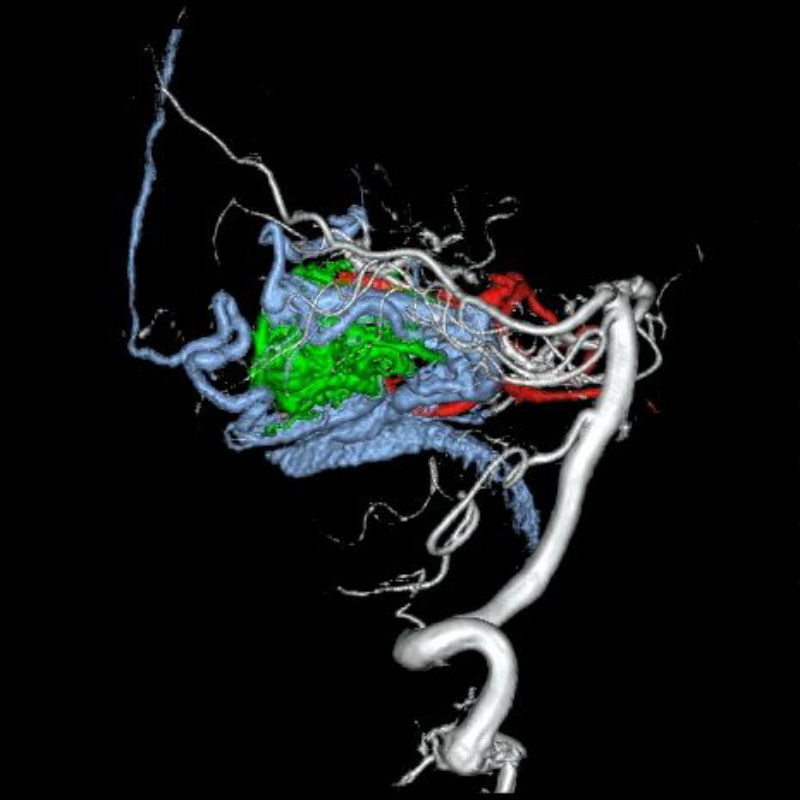

脳血管撮影

手術前